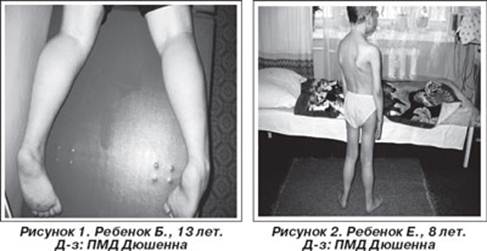

Псевдогипертрофическая злокачественная миодистрофия Дюшенна

Проявляется в возрасте 2тАФ5 лет. Течение быстро прогрессирующее, злокачественное. Обездвиженность больных, как правило, наступает в возрасте 14тАФ15 лет, смерть наступает в возрасте 15тАФ18 лет, больные редко живут более 25 лет. К 8-10 годам большинство детей нуждается в ортопедических аппаратах; к 12 годам большинство детей не могут ходить. Первые признаки заболевания проявляются в 1-3 года жизни слабостью мышц тазового пояса. Уже на 1-м году обращает на себя внимание отставание детей в моторном развитии. Они, как правило, с задержкой начинают садиться, вставать, ходить. Движения неловкие, при ходьбе дети неустойчивы, часто спотыкаются, падают. В 2-3 года появляются мышечная слабость, патологическая мышечная утомляемость, проявляющаяся при физической нагрузке - длительной ходьбе, подъеме на лестницу, изменение походки по типу ВлутинойВ». В этот период обращает на себя внимание своеобразная ВлстереотипнаяВ» динамика движений детей во время вставания из горизонтального положения, с положения на корточках или со стул